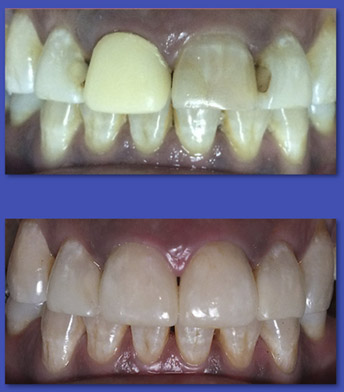

5. PRÓTESIS FIJA

(CORONAS Y PUENTES)

La prótesis Fija es el tratamiento indicado en aquellos casos en que la corona del diente está afectada completamente y se debe rehabilitar en forma íntegra, además en el caso de los puentes sirve para reponer de forma fija, dientes que fueron extraídos. La mayoría de las veces un diente con tratamiento de conducto requiere una corona para ser rehabilitado.

ANTES

DESPUÉS